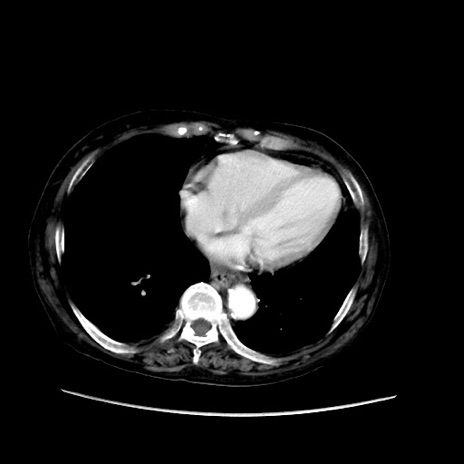

症例31(横断像)

【症例】80歳代 女性

【主訴】腹部膨満感

【現病歴】他院にて肝硬変にてフォロー中。1週間前から便秘、腹部膨満感、臍部腫瘤あり受診となる。

【既往歴】肝硬変

【身体所見】腹部膨隆あり、皮膚変化なし、疼痛なし。

【データ】WBC 4600、CRP 0.25